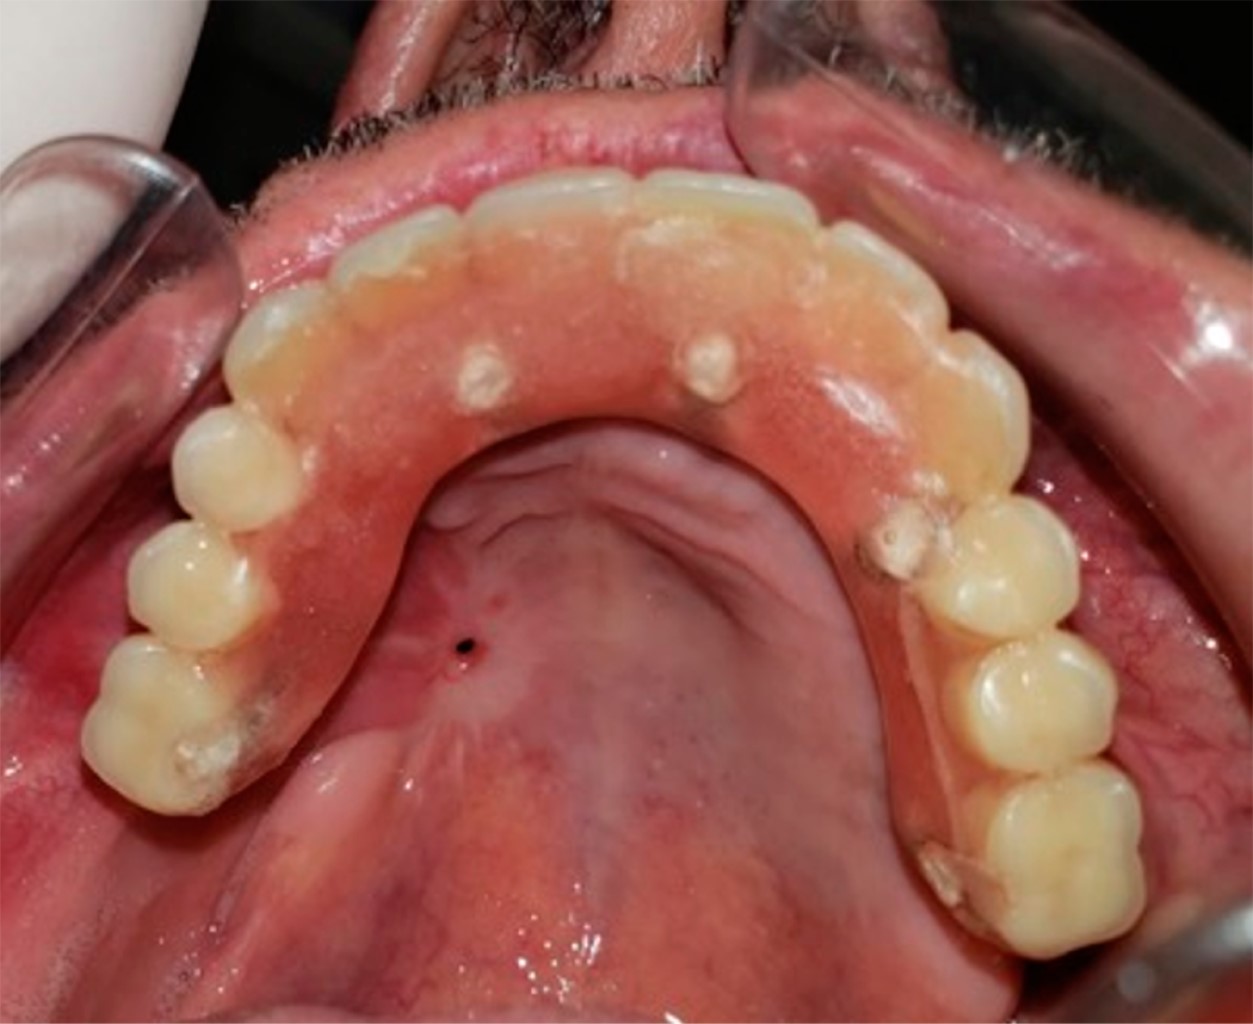

Figura 1

Figura 2

Figura 3

Figura 4

Figura 5

Figura 6

Figura 7

Figura 8